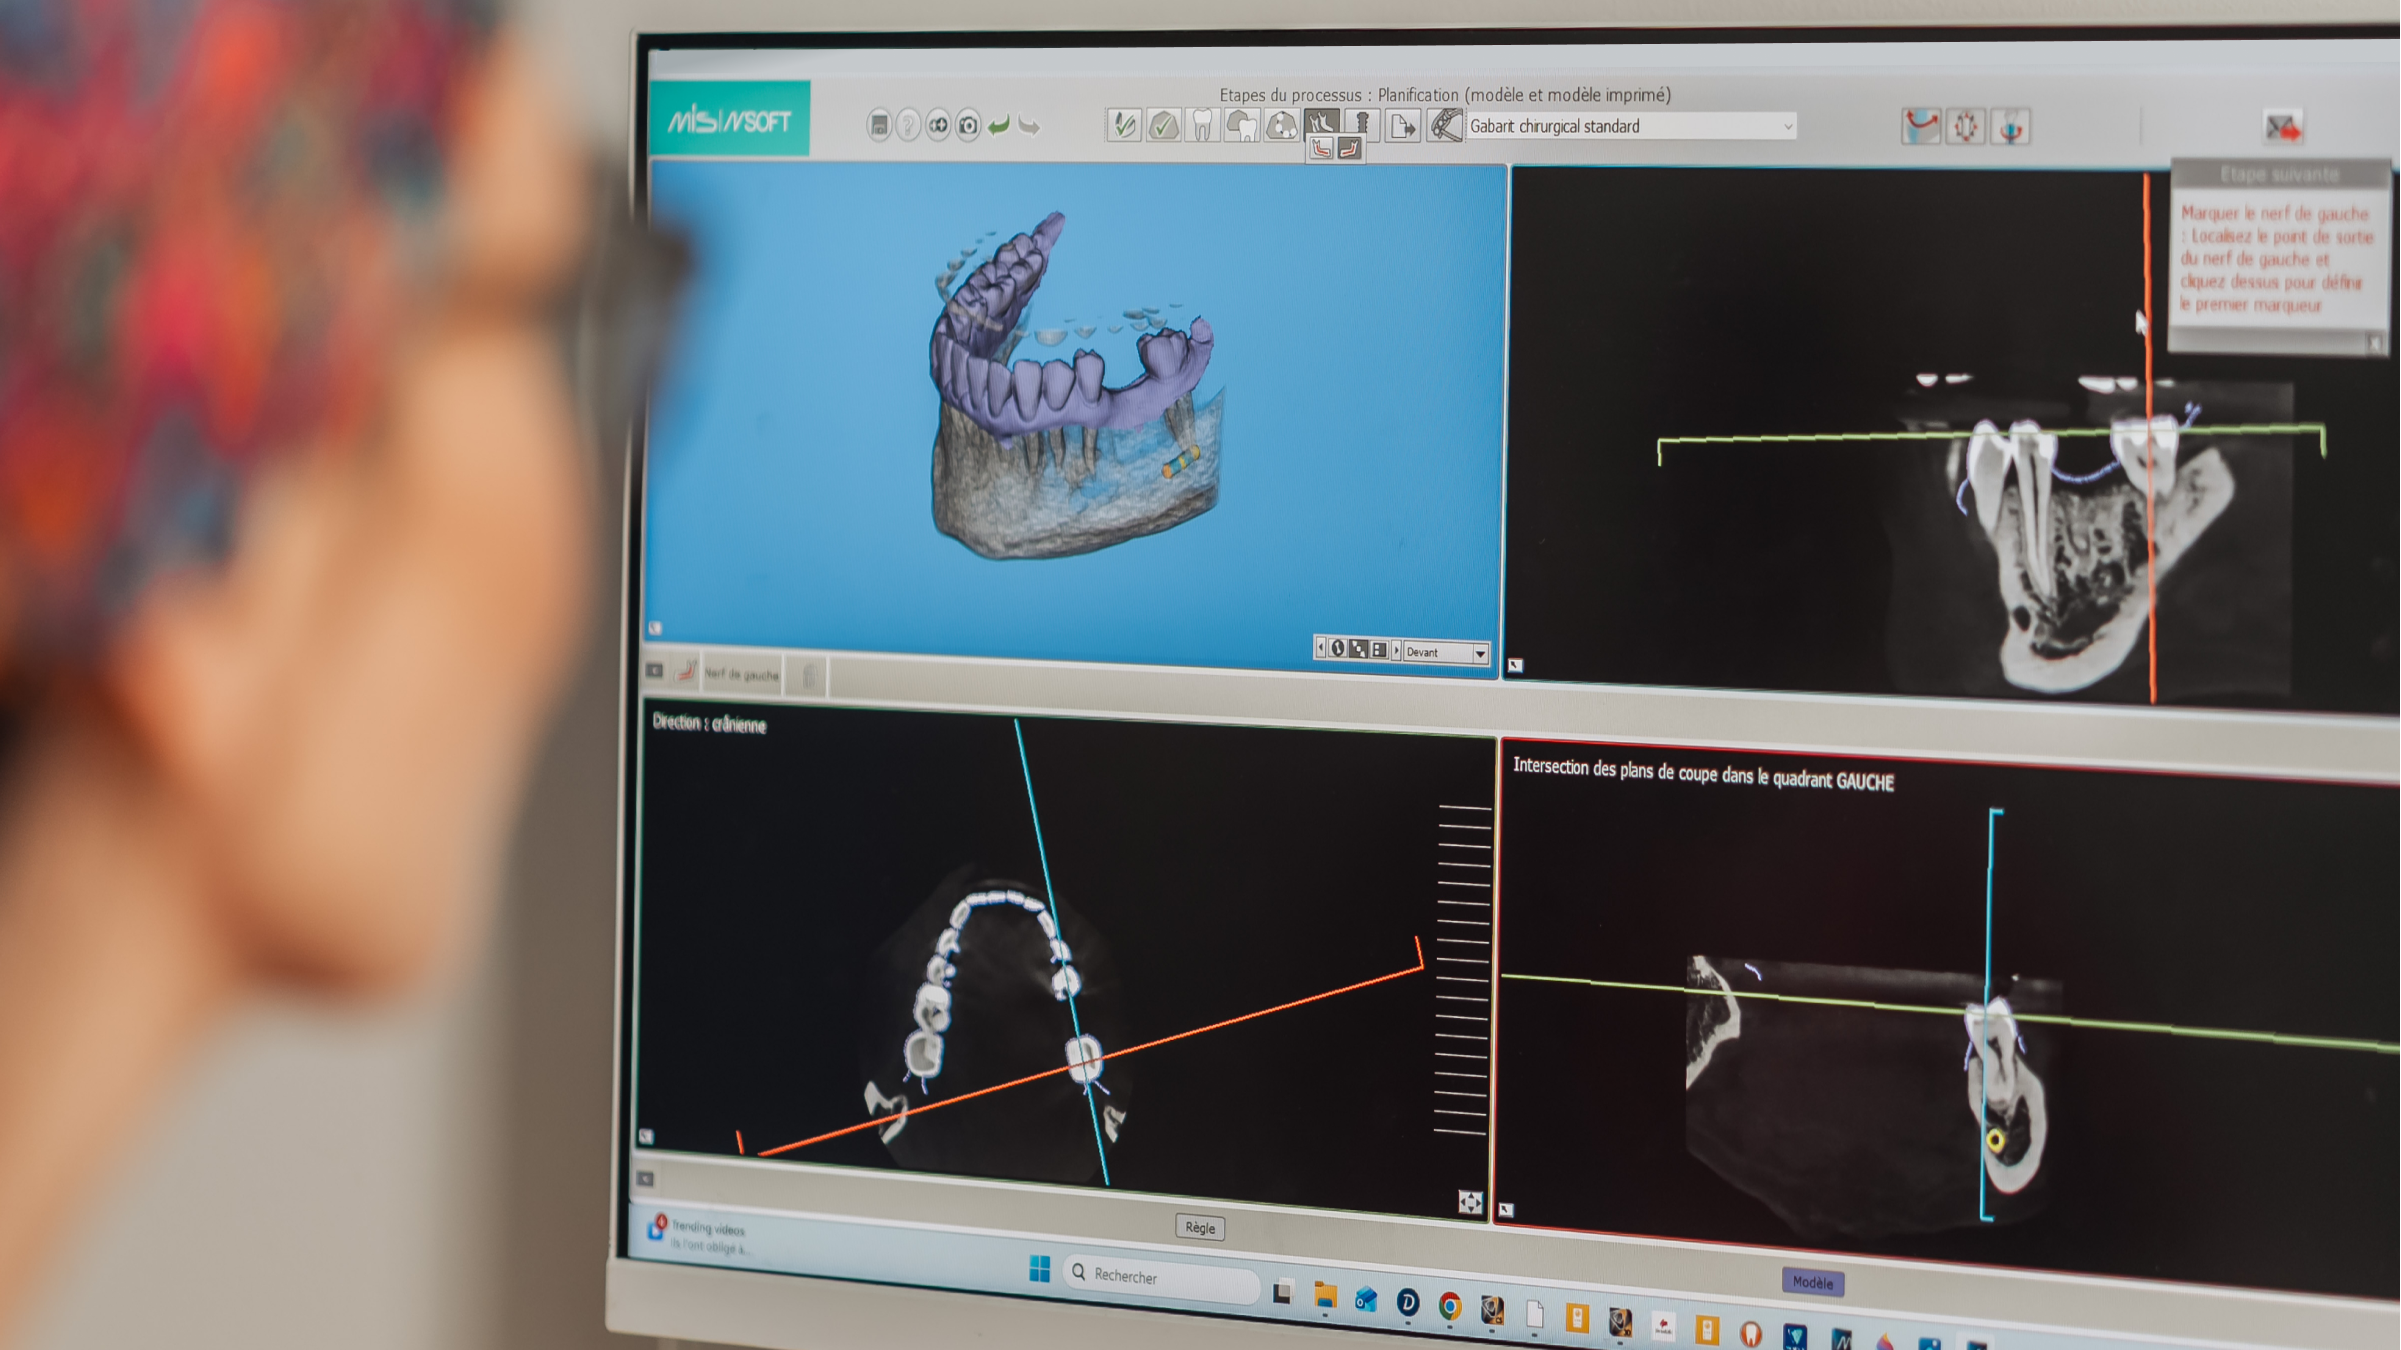

Logiciel de planification implantaire

Un logiciel de planification implantaire permet de préparer la pose d’un implant avec une grande précision, avant même l’intervention. En combinant les données d’une imagerie 3D (Cone Beam) et d’une empreinte numérique, il aide à définir la position idéale de l’implant en tenant compte de l’os, des dents voisines, des structures anatomiques et du projet prothétique.

Chirurgie guidée